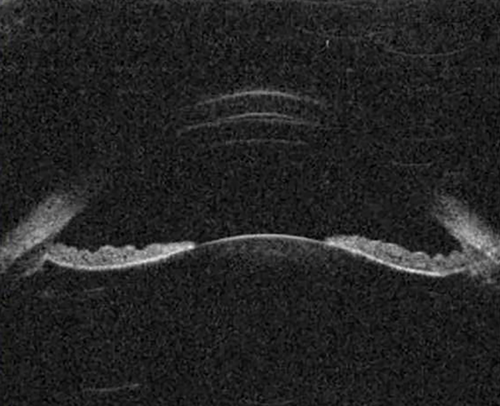

Figure 5: The peripheral iris is concave (bows backwards) in pigment dispersion syndrome.

Pigment dispersion syndrome (PDS)

PDS results from the dissemination of pigment granules from the posterior surface of the iris as a result of friction between it and the zonules and / or lens. PDS typically demonstrates an open angle and iris concavity with reverse pupil block consistent with the hypothesis that irido-zonular chafing is responsible for the dispersion of pigment particles (Figure 5).